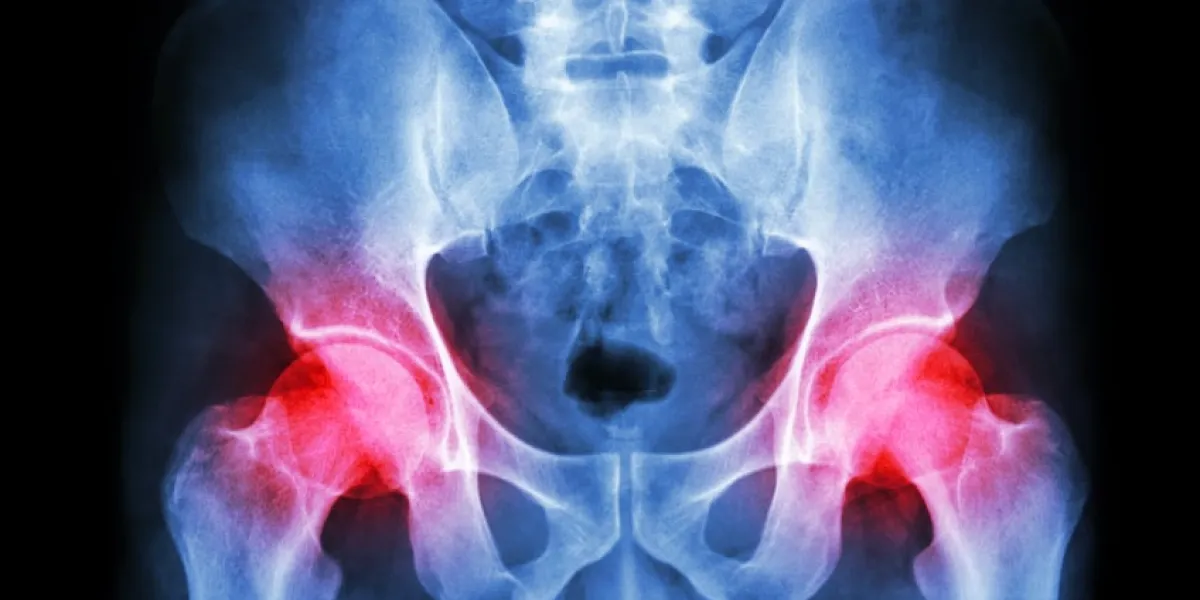

Bienvenue dans notre rubrique dédiée aux rhumatismes et aux problèmes articulaires. Cette section vise à fournir des informations complètes sur les affections rhumatismales, les douleurs articulaires, et les moyens de les prévenir et de les gérer. Explorez nos ressources pour comprendre les différents types de rhumatismes, les symptômes, les facteurs de risque, et les options de traitement disponibles. Nous sommes là pour vous accompagner dans la compréhension de ces conditions, pour vous donner des conseils pour soulager la douleur, et pour promouvoir une meilleure santé articulaire.